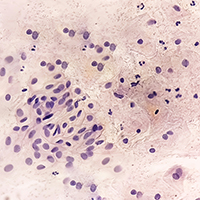

Коллектив ученых из МФТИ разработал метод, позволяющий с высокой точностью идентифицировать наиболее агрессивные раковые клетки, ответственные за распространение метастазов.

Ученые обнаружили ранее не известную противоопухолевую функцию белковой молекулы каспазы-2, участвующей в «самоуничтожении» клеток, то есть их программируемой гибели.